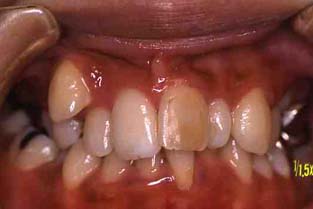

成人その3:八重歯と顎が狭い(唇側低位咬合,歯列狭窄) 22才,女性

矯正後(一年10ヶ月後)

正面

矯正治療後,歯並びもよくなって自信をとりもどした様でした。

矯正前とは違って,人前でも笑ったりおしゃべりしたりして大変明るくなりました!